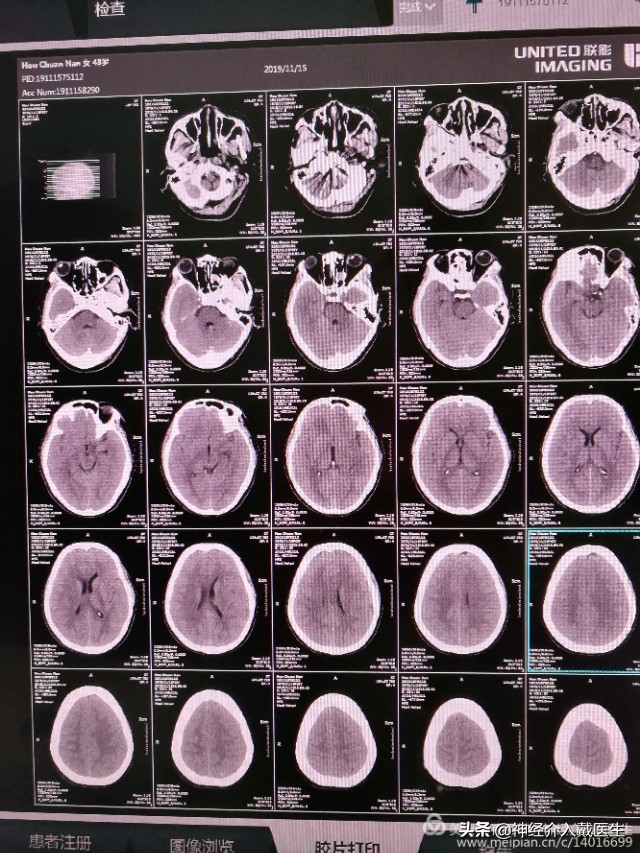

术后仍然剧烈头疼,复查头部CT排除颅内迟发出血。